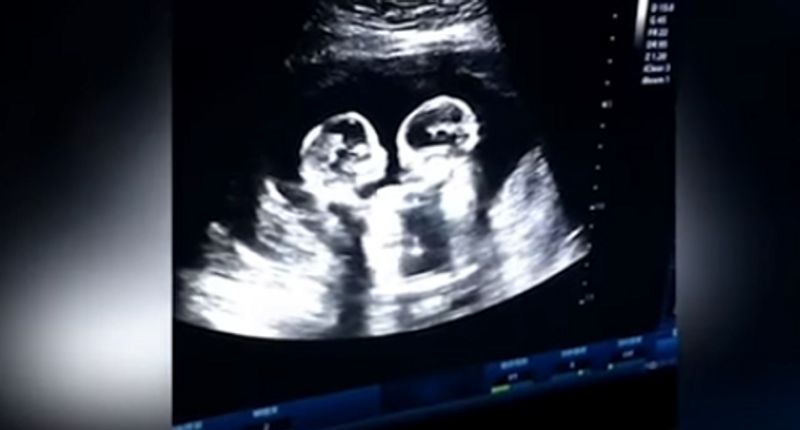

சீனாவை சேர்ந்த பெண் ஒருவர் நிறை மாத கர்ப்பிணியாக இருந்த நிலையில், அவரின் கருவில் உள்ள குழந்தைகளின் ஆரோக்கியத்தை பரிசோதனை செய்வதற்காக மருத்துவர் ஸ்கேன் செய்துள்ளார்.

அப்போது தாயின் வயிற்றில், இருந்த இரட்டை குழந்தைகள் ஒன்றோடு ஒன்று, அன்பாக சண்டையிட்டுள்ளது. இதனைக் கண்ட மருத்துவர் இன்ப அதிர்ச்சியில் உறைந்தார். மேலும் இந்த காட்சியைப் பதிவு செய்து இக்குழந்தையின் பெற்றோருக்கும் காட்டியுள்ளார்.